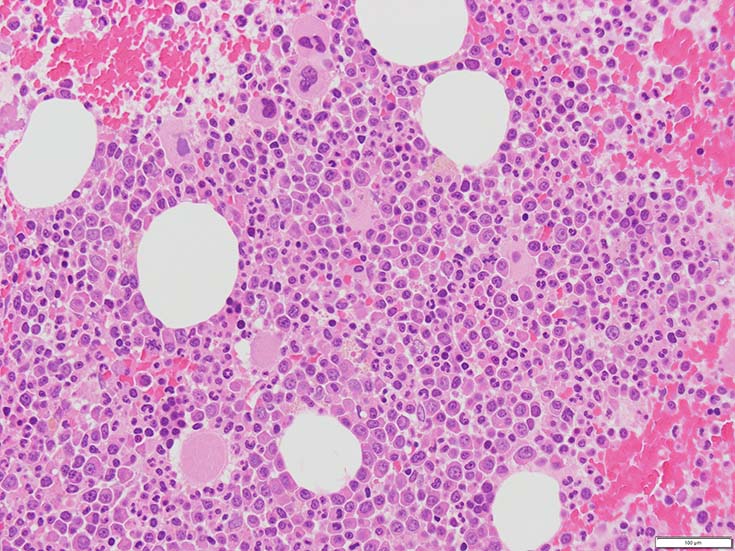

初診時の骨髄組織所見

thumb nail画像のクリックで大きな画像がみられます.

BM-f-01HE01.jpg BM-f-01HE02.jpg BM-f-01.jpg

HE染色および, Naphtol-ASD-CAE染色した骨髄クロット組織標本-->Naphtol-ASD-CAE染色, 載せガラス法のページをみる.

70-80%のhypercellular marrow. 3系統造血細胞が認められる. Naphtol-ASD-CAE染色で赤色にそまる顆粒球系細胞増生が顕著な骨髄組織.

promyelocytesなど幼若顆粒球系細胞の集簇がみられるが, 分葉好中球他, 成熟顆粒球(Naphtol-ASD-CAE染色は薄く染まる傾向あり)も多く認められacute leukaemiaの所見ではない.

単球(Naphtol-ASD-CAE染色陰性)が密に増殖する所見は骨髄組織には認められない(*1)